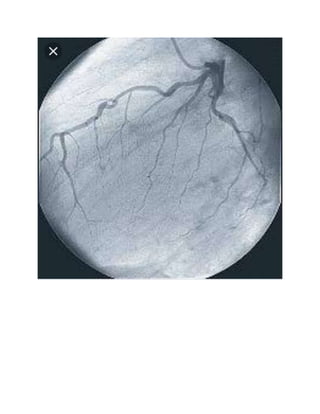

4). CORONARYANGIOGRAPHY

The reasonsfor coronaryangiographyinclude,assessingpresence of restrictiontobloodflow in

the coronary arteries andestablishingwhichpatientsare potential candidates forcoronary

arterybypassgrafting.